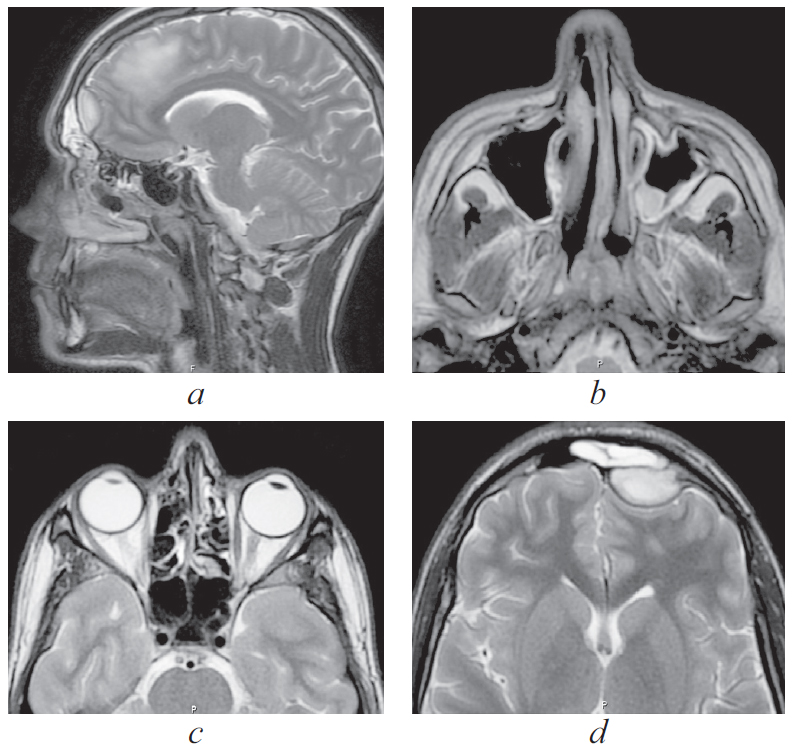

Риногенные внутричерепные осложнения, такие как абсцесс головного мозга и тромбоз вен и синусов головного мозга, по сей день остаются грозной, жизнеугрожающей патологией, не редко заканчивающейся летальным исходом, несмотря на широкое развитие антибактериальной терапии и приверженность пациентов к проводимому лечению. Нередко причиной развития внутричерепных осложнений служит обострение хронического воспалительного процесса в придаточных пазухах носа, тогда как острая ЛОР-патология синусов приводит к развитию риногенных осложнений лишь в небольшом проценте случаев. К сожалению, высокое развитие лучевой и лабораторной диагностики не всегда позволяет вовремя диагностировать данные состояния и оказать адекватную хирургическую помощь. В детском и подростковом возрасте важно выполнить своевременное полное и в то же время малоинвазивное, не приводящее к инвалидизации, хирургическое пособие. Анализ зарубежной литературы последних лет показывает, что нейрохирургические операции в различном объеме (от трепанопункции головного мозга до краниотомии) встречаются в подавляющем большинстве случаев лечения риногенных внутричерепных осложнений. В статье приводятся два клинических случая успешно пролеченных в отделении оториноларингологии Санкт-Петербургского государственного педиатрического медицинского университета пациентов с внутричерепными осложнениями без высокотравматичной нейрохирургической операции. Комбинация эндоназальной эндоскопической операции и массивной адекватной консервативной терапии (антибиотикотерапия в сочетании с применением антикоагулянтов при синус-тромбозе) позволяет добиться выздоровления пациента без обращения к нейрохирургическому вмешательству.